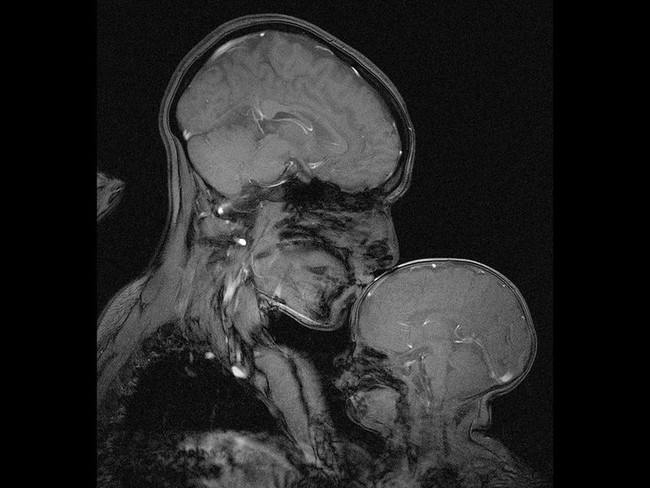

Quizás ya hayáis visto esta imagen antes. Quizás la imagen no, pero sí el gesto. Una madre dando un beso a su pequeño mientras lo acompaña en ese mágico instante en el que se va dejando ir, preso del sueño y el descanso.

El bebé se duerme mientras ella posa sus labios sobre su frente porque siente la necesidad de darle un beso, de oler su cabecita y sentir su calorcito en su boca.

Y es probable que no lo hayáis visto nunca de esta manera, en una imagen instantánea que, escondiendo mucho, muestra tanto. No sabemos quiénes son al verlos, no podemos reconocer más que sus siluetas, pero sí vemos su interior, y sí vemos el amor, en una imagen que quizás os genere esta duda: ¿cuál es la historia detrás de esta resonancia magnética?

Rebecca Saxe y Atsushi Takahashi son dos investigadores del Departamento del Cerebro y Ciencias Cognitivas del MIT. Según explica Rebecca en Smithsonian, son necesarios varios minutos para conseguir esta imagen, porque un leve movimiento puede hacer que se vean zonas borrosas y que entonces no se consiga ver lo que se busca.

La madre. La respuesta es la madre. Su presencia, su abrazo, fue lo que el bebé necesitó para dejar de llorar, calmarse, poder estar dentro del aparato y finalmente dejarse llevar, dormirse, y hacer que ese momento tan mágico y universal quedara para la posteridad como nunca había sucedido antes: el amor de una madre hacia su hijo, y viceversa, en una resonancia magnética.

"Esta imagen en particular de RM no se hizo con fines de diagnóstico, ni siquiera para la ciencia. Nadie, que yo sepa, había hecho una imagen de MR de una madre y un niño. Hicimos este porque queríamos verlo", ha dicho Rebecca.

Se adaptó la máquina para que pudieran entrar los dos, y permanecer juntos, y aunque en un primer momento el pequeño dijo que no quería estar ahí, el estar con mamá sirvió para que pronto se calmara y acabara por dormirse.

Y aquí está la gracia, que cada persona ve algo diferente al observarla. Unos verán la parte más científica, las diferencias entre los cerebros de una persona adulta y madura y de un bebé cuyo desarrollo está aún por llegar; otros se quedarán con el gesto universal de amor de una madre y su bebé, aparentemente anónimos.

Y luego está lo que sugiera Rebecca, la madre, que asegura ver una imagen antigua hecha nueva. Una madre y su niño en un poderoso símbolo de amor e inocencia, belleza y fertilidad, que se entremezcla con valores que también le son propios, por ser científica, pero que en la sociedad parecen estar contrapuestos: investigación e intelecto, progreso y poder.